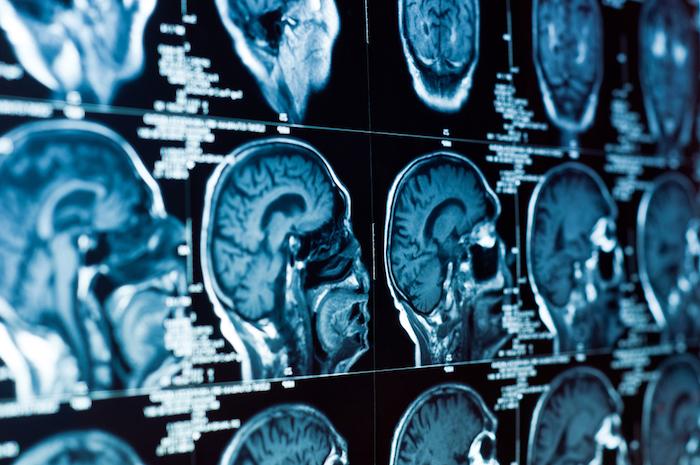

La tumeur cérébrale

Les signes dépendent de la localisation de la tumeur dans le cerveau et de son évolution. Leur survenue peut être progressive ou au contraire soudaine. La survenue soudaine de troubles neurologiques comme des troubles de la vision ou de la parole, de même qu’une crise d’épilepsie chez une personne en bonne santé doit faire consulter un médecin sans délai.

La tumeur cérébrale représente 2 % de l’ensemble des cancers et touche plus de 240 000 personnes en Europe. 5 000 nouveaux cas de tumeurs primitives malignes du cerveau, dont 2500 à 3000 nouveaux cas de gliomes sont diagnostiqués chaque année en France, selon l'Institut du Cerveau et de la Moelle Epinière (ICM). La tumeur cérébrale est également la deuxième cause de cancer chez l’enfant, après les cancers du sang comme les leucémies.